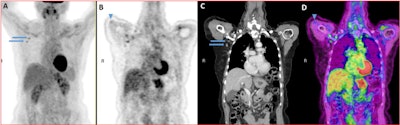

Drs. Michal Eifer and Yael Eshet of Sheba Medical Center in Tel-Hashomer, Israel, shared an image of a 72-year-old woman who underwent a follow-up FDG-PET/CT scan after left lumpectomy, sentinel lymph node biopsy, and chemotherapy for HER2+ breast cancer in 2017. The woman received the Pfizer COVID-19 vaccine in her right deltoid muscle 10 days before the scan.

The scan was normal except for some uptake in that muscle and in two right axillary lymph nodes which were of normal size -- findings that likely show effects of the recent COVID-19 vaccine rather than recurrent breast cancer, according to the two researchers.